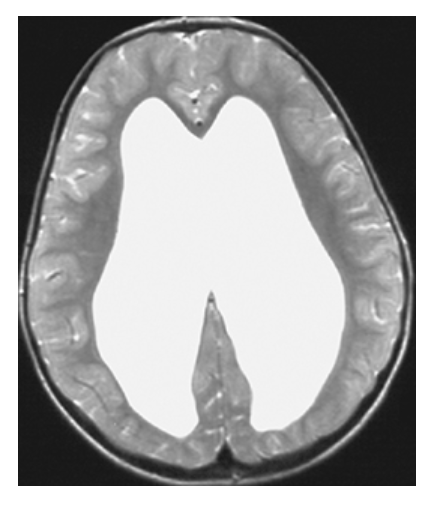

Hydrocephalus. T2-weighted axial MRI shows high-signal CSF of the markedly dilated lateral ventricles.